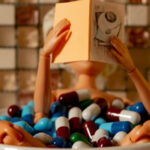

Bárbarah Constantino - Silêncio Medicado - Fotografia digital - 30x40 cm – São Paulo - SP - 2025

Bárbarah Constantino - Silêncio Medicado - Fotografia digital - 30x40 cm – São Paulo - SP - 2025

Bárbarah Constantino - Silêncio Medicado - Fotografia digital - 30x40 cm – São Paulo - SP - 2025